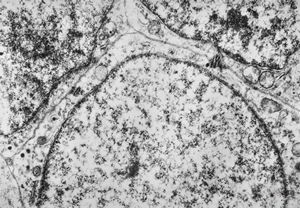

![F,23y. | n.suralis - hypertrophic demyelinating neuropathy [onion bulb] F,23y. | n.suralis - hypertrophic demyelinating neuropathy [onion bulb]](../img/OGDEM/015 Soft tissues/0076.jpg)

F,23y. | n.suralis - hypertrophic demyelinating neuropathy [onion bulb]